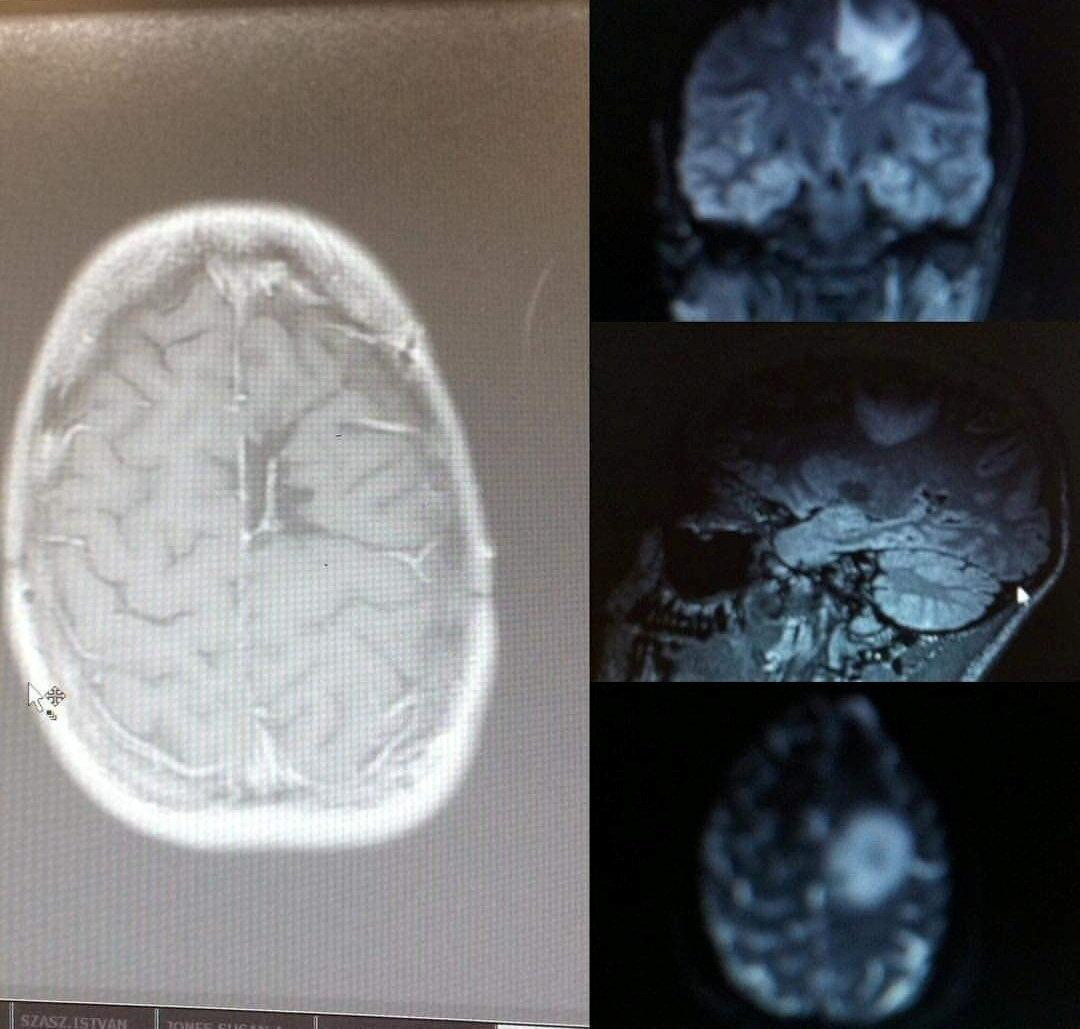

Kada se Amy Carr onesvijestila u svojoj sobi na prizor pauka, liječnici su njezin slučaj otpisali kao običan strah, odnosno fobiju. No kada je tada petnaestogodišnjakinja, sada bivša nogometna zvijezda Engleske, još dva puta izgubila svijest u teretani, liječnici su otkrili zastrašujuću istinu. Snimke njezine glave iz 2013. godine već su tada otkrile agresivni tumor mozga astrocitom, u četvrtom stupnju i veličine loptice za golf, piše The Sun.

Tinejdžerica je tada bila podvrgnuta inovativnom zahvatu, pri kojem je bila budna dok su joj liječnici operirali mozak. Osim toga, primala je i zračenje te kemoterapiju, a prognoza za njezino preživljavanje bila je 95 posto. No nakon zahvata osam dana nije mogla govoriti ni hodati, a kada se malo oporavila, počela je komunicirati na srednjoškolskoj razini francuskog jezika, a zatim se ubrzo ponovno vratila engleskom. Nakon dugog i mukotrpnog liječenja rečeno joj je da je slobodna od bolesti.